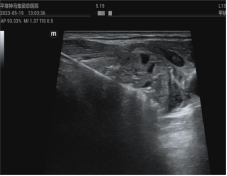

熱消融技術(shù)是指在超聲實(shí)時(shí)引導(dǎo)下,將消融針插入病灶內(nèi),產(chǎn)生的高溫在短時(shí)間內(nèi)使病灶組織凝固壞死的方法。這一方法操作微創(chuàng)精準(zhǔn),效率高,范圍可控,不良反應(yīng)小,可重復(fù)性強(qiáng),實(shí)現(xiàn)了治療的微創(chuàng)、美觀、有效、安全的完美結(jié)合??剖议_展甲狀腺、乳腺、肝臟、子宮、淋巴結(jié)等多臟器實(shí)體腫瘤的熱消融治療多年,積累了豐富的臨床診治經(jīng)驗(yàn),患者受益,提高了患者的生活質(zhì)量。